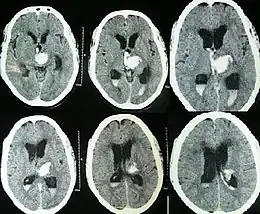

Hydrocephalus as seen on a CT scan of the brain. The black areas in the middle of the brain (the lateral ventricles) are abnormally large and filled with fluid.

Spontaneous intracerebral and intraventricular hemorrhage with hydrocephalus shown on CT scan[34]